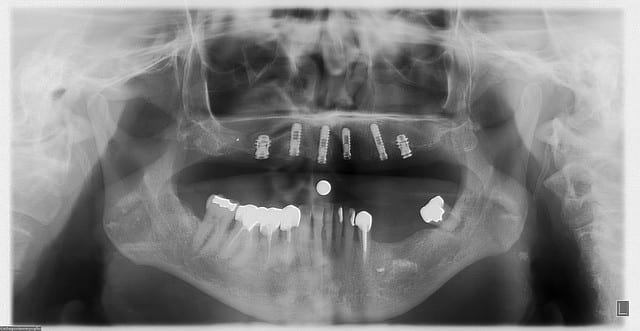

allez, dans ma série, "je remets des sujets" je vous donne quelques nouvelles de ce cas

la raison et vos conseils me sont revenus, j'ai posé hier 2 implants supplémentaires en 17 et 27 (sans les facturer à mon patient)

ce qui me frappe, tout de même, avec les quelques radios prises, c'est la cicatrisation osseuse au niveau de ceux en 15 et 25 (cf panos jour de la pose/3mois/4mois et les "zooms" pose/4mois)

en 17, non pas dans le sinus...à ras, mais pas dans le sinus